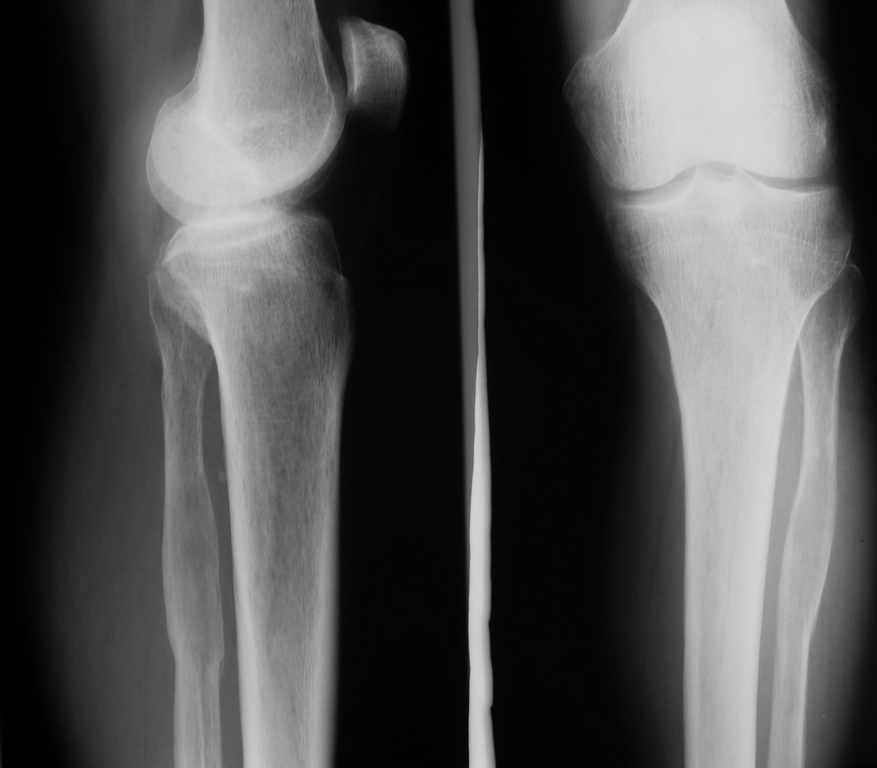

Ещё одно клиническое наблюдение - лимфома кости, до и после ПХТ и лучевой терапии.